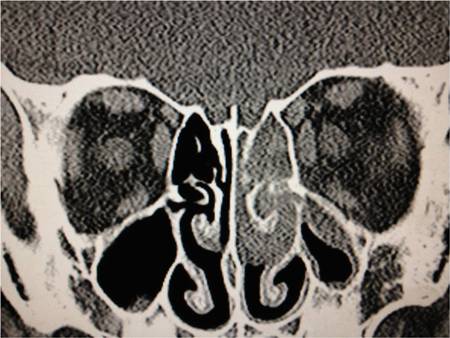

[Figure caption and citation for the preceding image starts]: Coronal CT post contrast: opacified ethmoid and frontoethmoidal recess on the left sideFrom the personal collections of H. Jane Kim, MD, and Robert Kersten, MD, UCSF; used with permission [Citation ends].

Orbital cellulitis: inflammation of orbital tissues located deep to the septum.

inflammation of peri-orbital or orbital tissue; sub-periosteal abscess (commonly superomedial or inferomedial); sinusitis